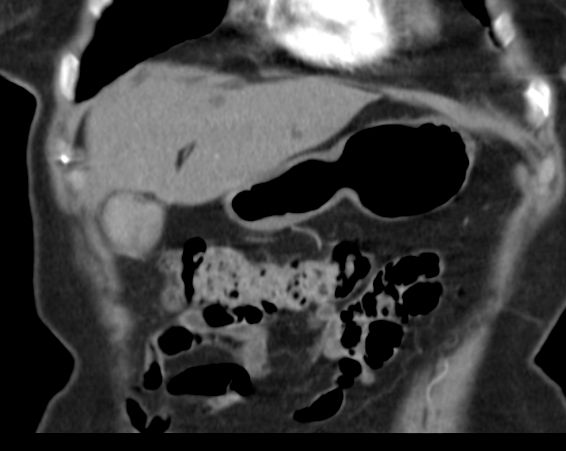

Beispiel: CT eines Funduskarzinoms in einer

Stein-Blase ![]() |

![]() |